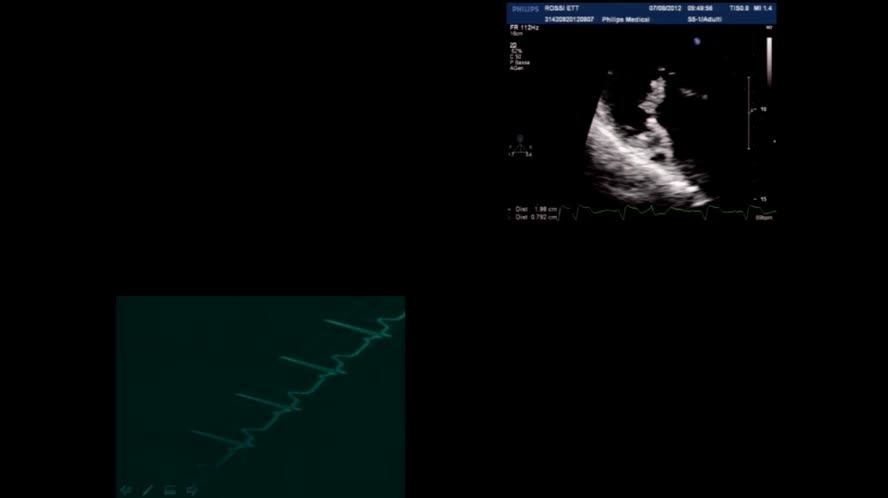

Diagnosi ecografica di endocardite

Congresso

: Ecografia Clinica nelle Malattie Infettive

Autori

: E. Puccioni |

Data

: 21 marzo, 2016 |

Lingua

: ITA |